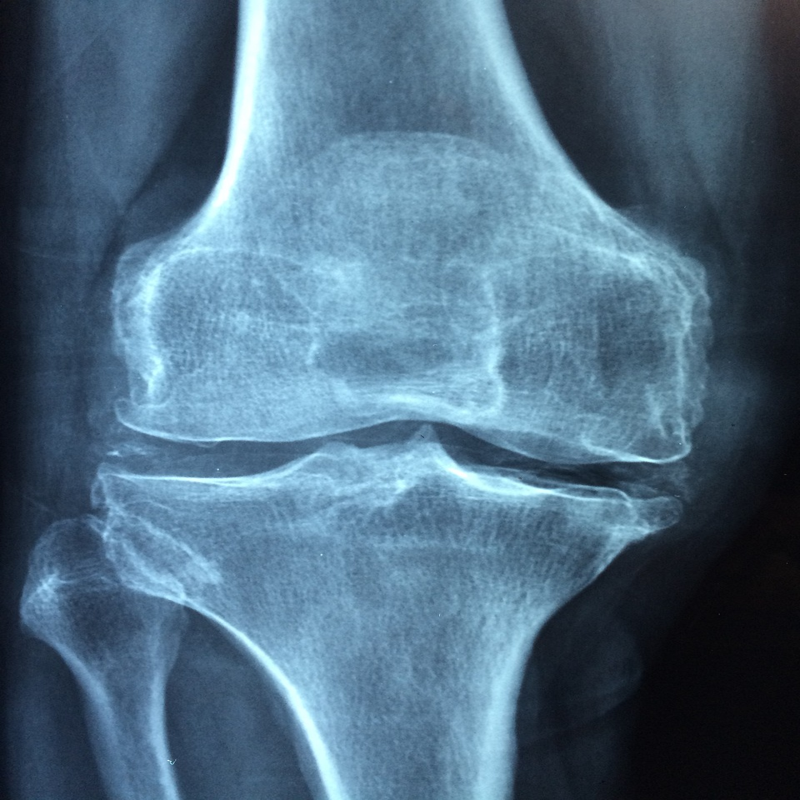

골다공증은 뼈의 강도가 약해져서 골절 위험이 증가하는 질환을 말합니다. 우리 뼈는 마치 은행처럼 끊임없이 오래된 뼈를 부수고 새로운 뼈를 만들어내는 과정을 반복하는데요, 골다공증은 이러한 과정에서 균형이 깨져 뼈의 형성보다 파괴되는 속도가 빨라지면서 발생합니다.

골다공증 진단은 골밀도 검사를 통해 이루어집니다. 골밀도 검사는 우리 뼈의 강도를 나타내는 중요한 지표로, 이 수치를 통해 현재 골다공증 진행 정도를 파악하고 적절한 치료 계획을 세울 수 있습니다.

만약 골밀도 검사 결과 T-점수가 -2.5 이하로 나왔다면 이미 골다공증이 상당히 진행된 상태이므로, 전문의와 상담 후 적극적인 치료를 시작해야 합니다.